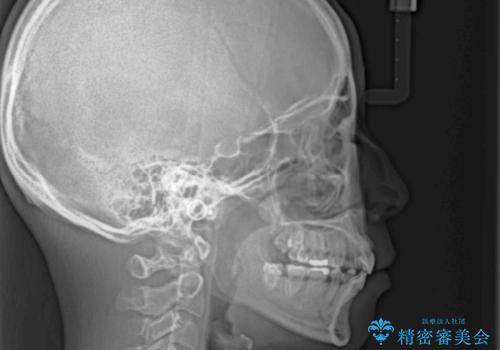

- 口元の閉じにくさと、前歯のでこぼこの歯並びを気にして来院された患者様です。

口元を積極的に引っ込めるために、上下左右の小臼歯計4本を抜歯することとしました。

セオリーでは第一小臼歯を抜歯しますが、上下右側は第二小臼歯に銀歯が装着されているため、第二小臼歯を抜歯することとしました。

上下正中を左右対称に揃えるため、アンカースクリューや補助装置を使用しながら口元を下げていくこととしました。

積極的に前歯を牽引したことで、口元の閉じにくさは顕著に改善され、横顔のシルエットが大幅に変化しました。